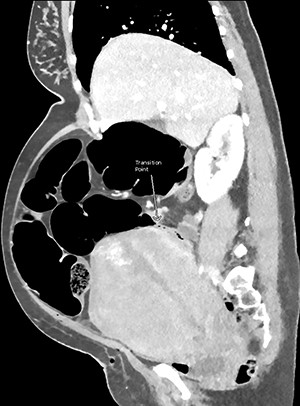

CT images suggested complete obstruction of the sigmoid colon secondary to impingement by polymyomatous uterus (see Fig. 2). The transition point was directly posterior to a large fibroid which appeared necrotic, shown in Fig. 3. Although the pathology was arguably mechanical, it was decided to trial conservative management, consisting of NGT insertion, enemas, laxatives, electrolyte optimization, cessation of constipating medication and frequent mobilization. Within 24 h, the patient began to pass flatus. Her symptoms resolved completely after 72 h and she was discharged with gynaecology follow-up.

CT abdomen and pelvis with venous phase contrast, sagittal view. Abrupt collapse of the gas-filled sigmoid colon is shown posterior to the enlarged uterus. Subcutaneous gas in the anterior abdominal wall is from recent surgery.